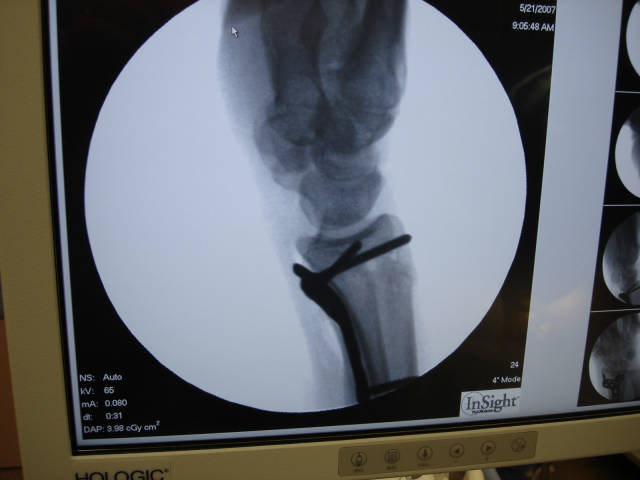

6. 应用 X 线透视确认钢板和远排螺钉的位置:

9. 术中 X 线影像证实,骨折最终获得解剖复位,钢板螺钉的位置满意: